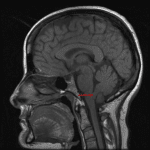

Age: 42

Sex: Female

Indication: Headache

- Intraventricular mass in the inferior aspect of the fourth ventricle measuring 12 x 10 x 10 mm

- No corresponding enhancement or restricted diffusion

- No hydrocephalus

- T2 hyperintense lesion adjacent to the frontal horn of the left lateral ventricle (patient had a history of multiple sclerosis)

- Dilated perivascular space in the right basal ganglia

Subependymoma